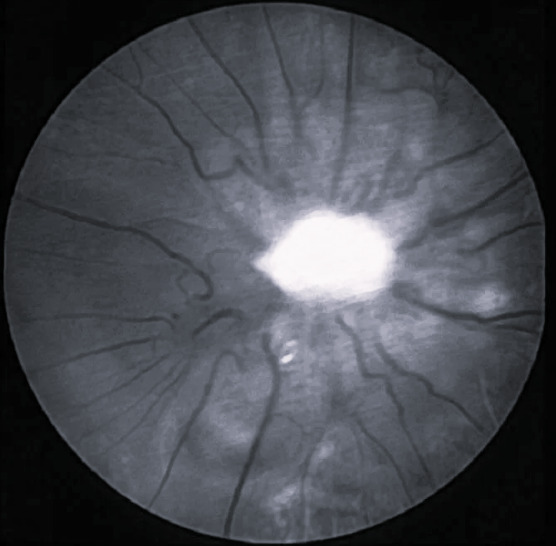

Атрофия зрительного нерва москва